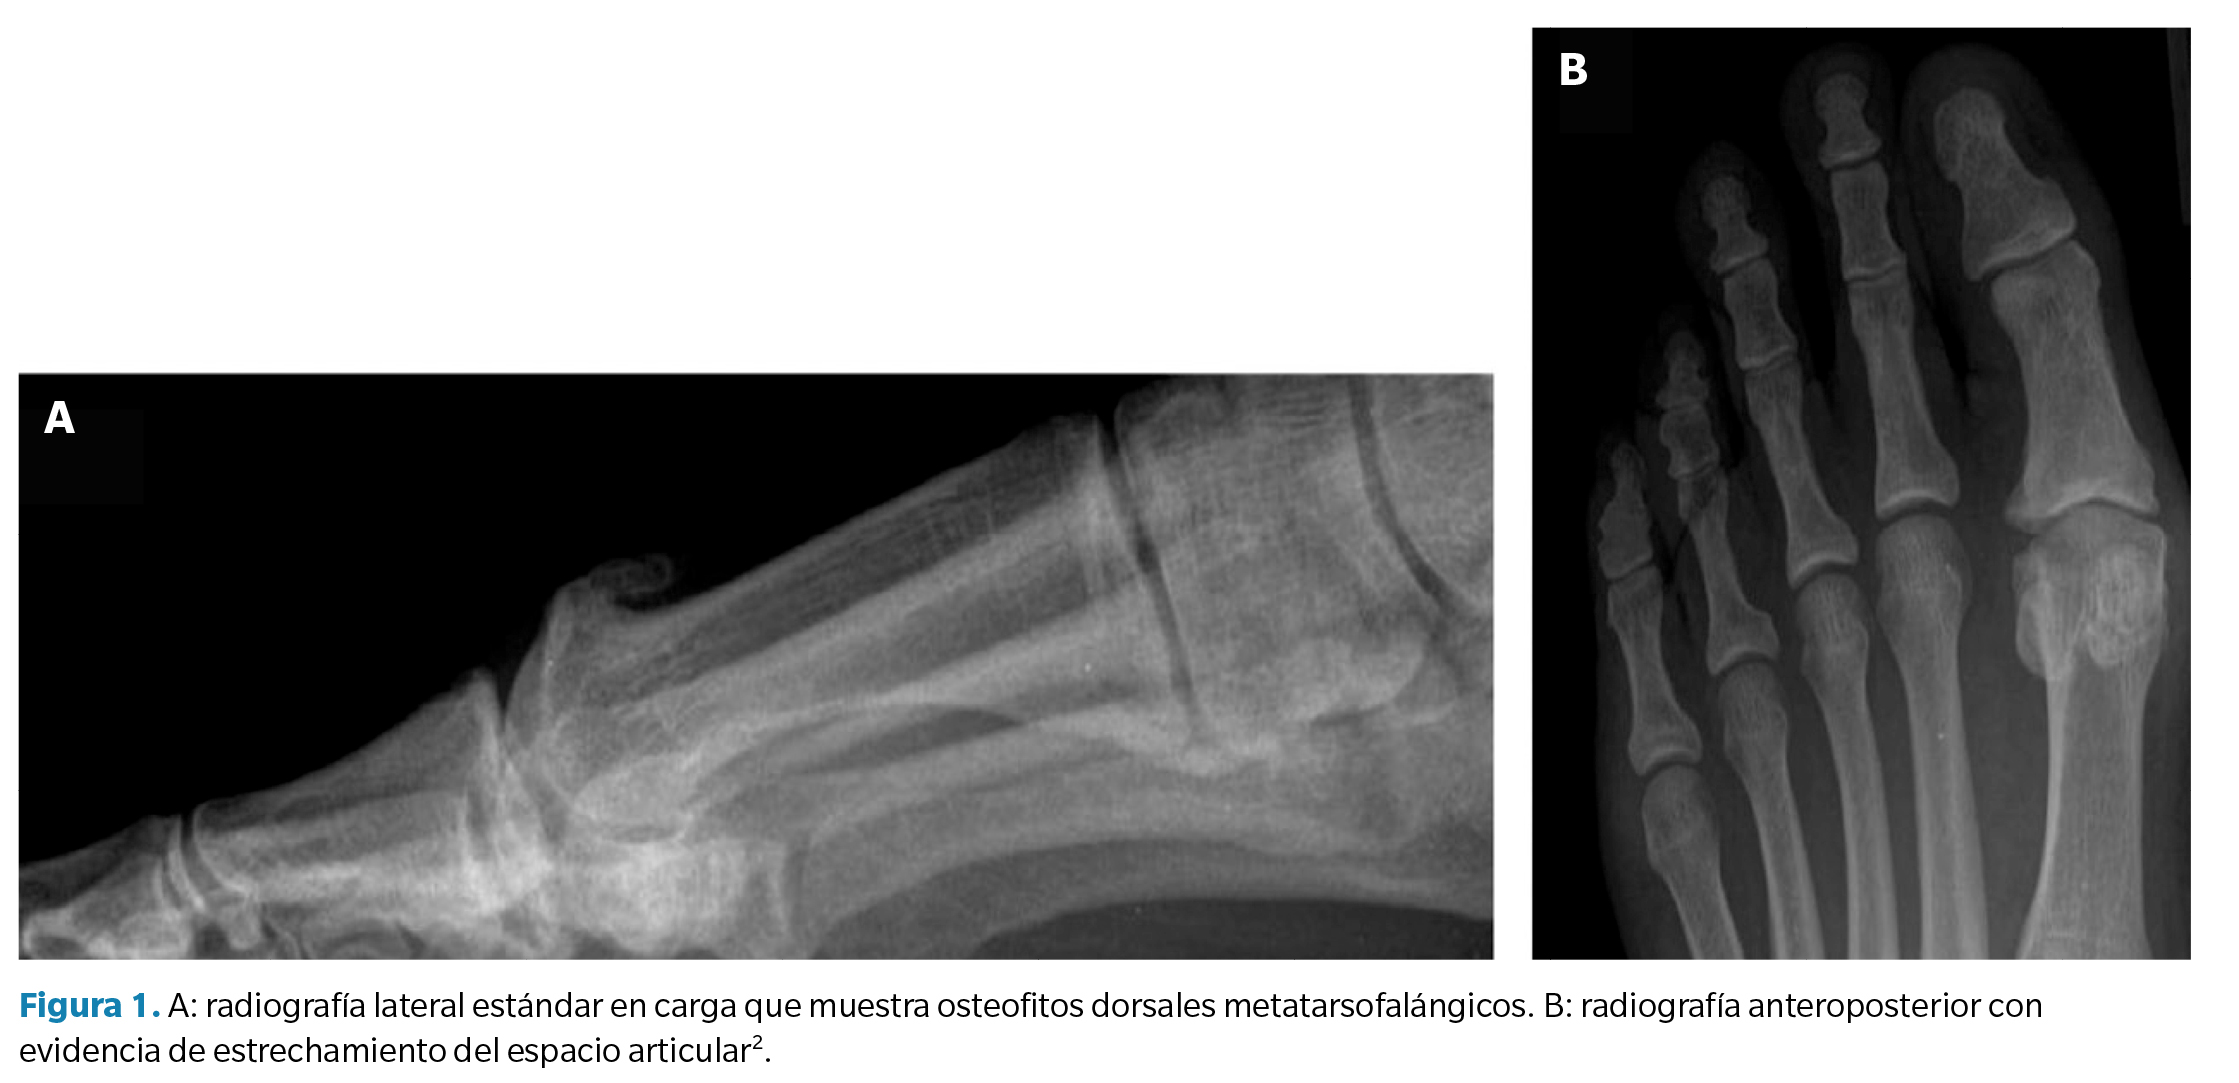

La evaluación radiológica del HR se basa en una radiografía en proyección anteroposterior y lateral en carga (Figura 1). Estas pruebas de imagen permiten la toma de decisiones quirúrgicas enfocándose hacia técnicas de conservación articular (queilectomía), osteotomías capitales, artroplastias o técnicas de fusión articular (artrodesis) en enfermedades más desarrolladas. Se recomienda la utilización de radiografías laterales para la identificación de osteofitos dorsales y para la valoración de la reducción del espacio articular de la primera AMT.

La clasificación de Coughlin es una herramienta útil para la evaluación del HR que combina hallazgos clínicos y radiográficos. Se basa en cinco grados de severidad, que van desde la pérdida mínima de movimiento en la primera AMT hasta la anquilosis completa de la articulación. Esta clasificación se utiliza para establecer un plan de tratamiento y determinar la mejor opción quirúrgica para el paciente. Esta clasificación se basa en criterios clínicos, como la limitación de la DF pasiva, así como en criterios radiográficos, como la presencia de osteofitos y la reducción del espacio articular de la primera AMT. A continuación, en la Tabla 1 se muestran los cinco grados de severidad de la clasificación de Coughlin.